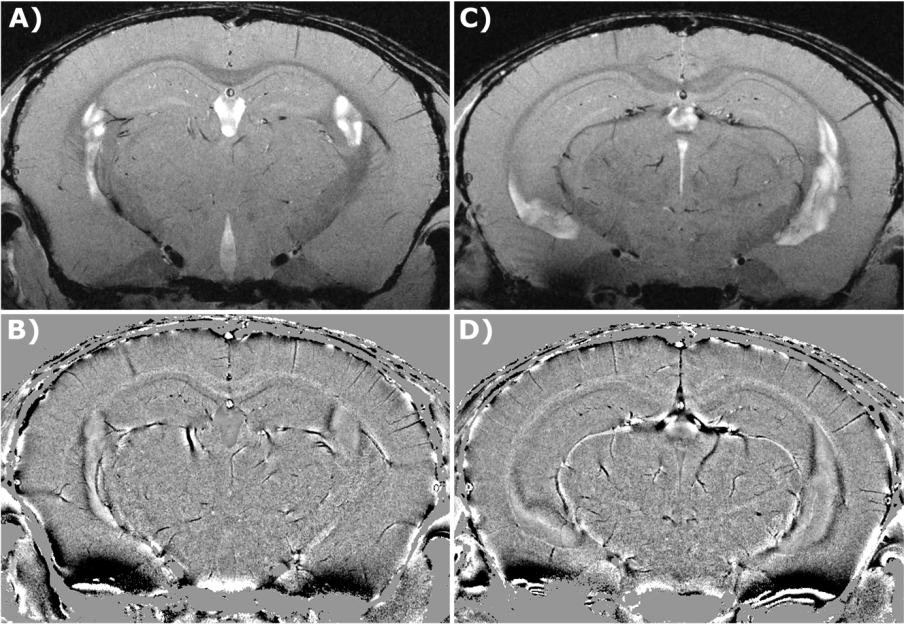

Ultra high resolution T2* weighted in vivo mouse brain data acquired at 15.2 Tesla with an MRI CryoProbe. Method: FLASH, Resolution: (20 x 20) µm², Slice Thickness: 150 µm, Slices: 7, Scan time: 21 min. A/C) Magnitude images, two different slices. B/D) Corresponding phase images.

In addition to BOLD imaging, further imaging applications which rely on high susceptibility effects combined with a high SNR and therefore benefit from UHF, are Susceptibility Weighted Imaging (SWI) and Quantitative Susceptibility Mapping (QSM) [7]. QSM can for example be applied in vivo to study the microvasculature in animal stroke models [8].